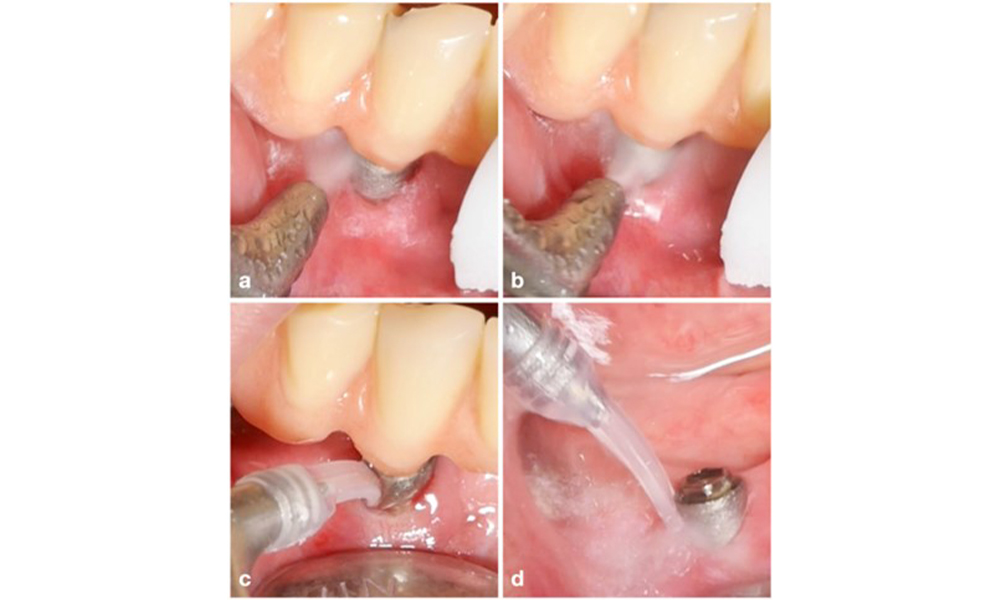

Management of peri-implantitis at implants judged as treatable consists of a non-surgical phase, which is often followed by surgical intervention. For the non-surgical approach, similar measures as those applied for the treatment of peri-implant mucositis are used; based on laboratory experiments air-polishing devices with a subgingival nozzle appear to provide certain advantages in terms of biofilm removal, compared to hand- or ultrasonic instruments (Herrera et al. 2023; Moharrami et al. 2019; Ronay et al. 2017) (figure 9).

Patient case with peri-implantitis. The non-surgical treatment is performed by using the supragingival (a-b) and subgingival handpiece of an air-polishing device (c-d). Removing the supra-construction provides better access to the implant surface (d).

Figure 9. Patient case with peri-implantitis. The non-surgical treatment is performed by using the supragingival (a-b) and subgingival handpiece of an air-polishing device (c-d). Removing the supra-construction provides better access to the implant surface (d).